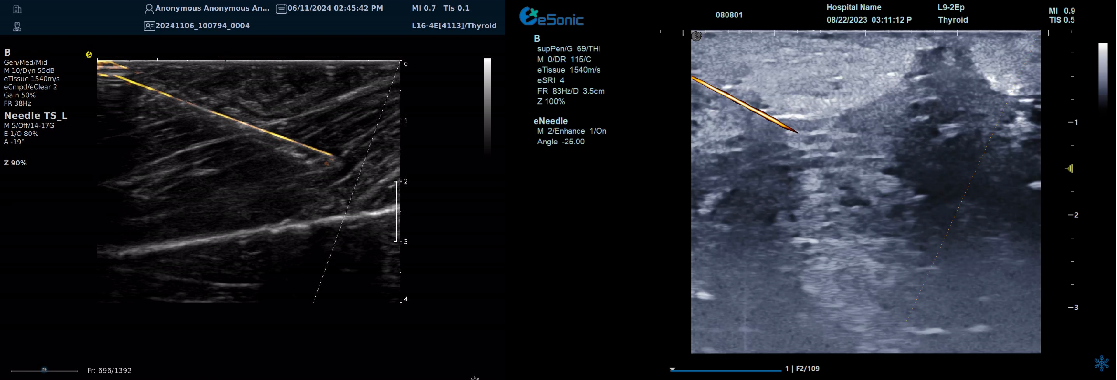

智能介入解决方案-----  穿刺针增强技术

?指示针尖位置、提高针道显示

?穿刺针智能彩色map,有效区分针尖与神经肌腱组织,

尤其在热消融时空化组织不影响针尖显示

?无磁导航:精准制导、自动追踪

?智能识别、路径预判

--引导延长线随针尖转动实时偏转

image.pngimage.png